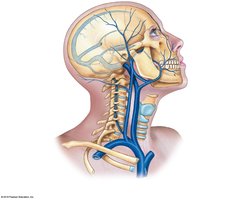

Venous Return from the Head, Neck, and Upper Limb

Blood from the head and neck drains into the internal and external jugular veins and vertebral veins, which empty into the brachiocephalic veins and then the superior vena cava. The upper limb is drained by superficial (cephalic, basilic) and deep (radial, ulnar, brachial) veins.